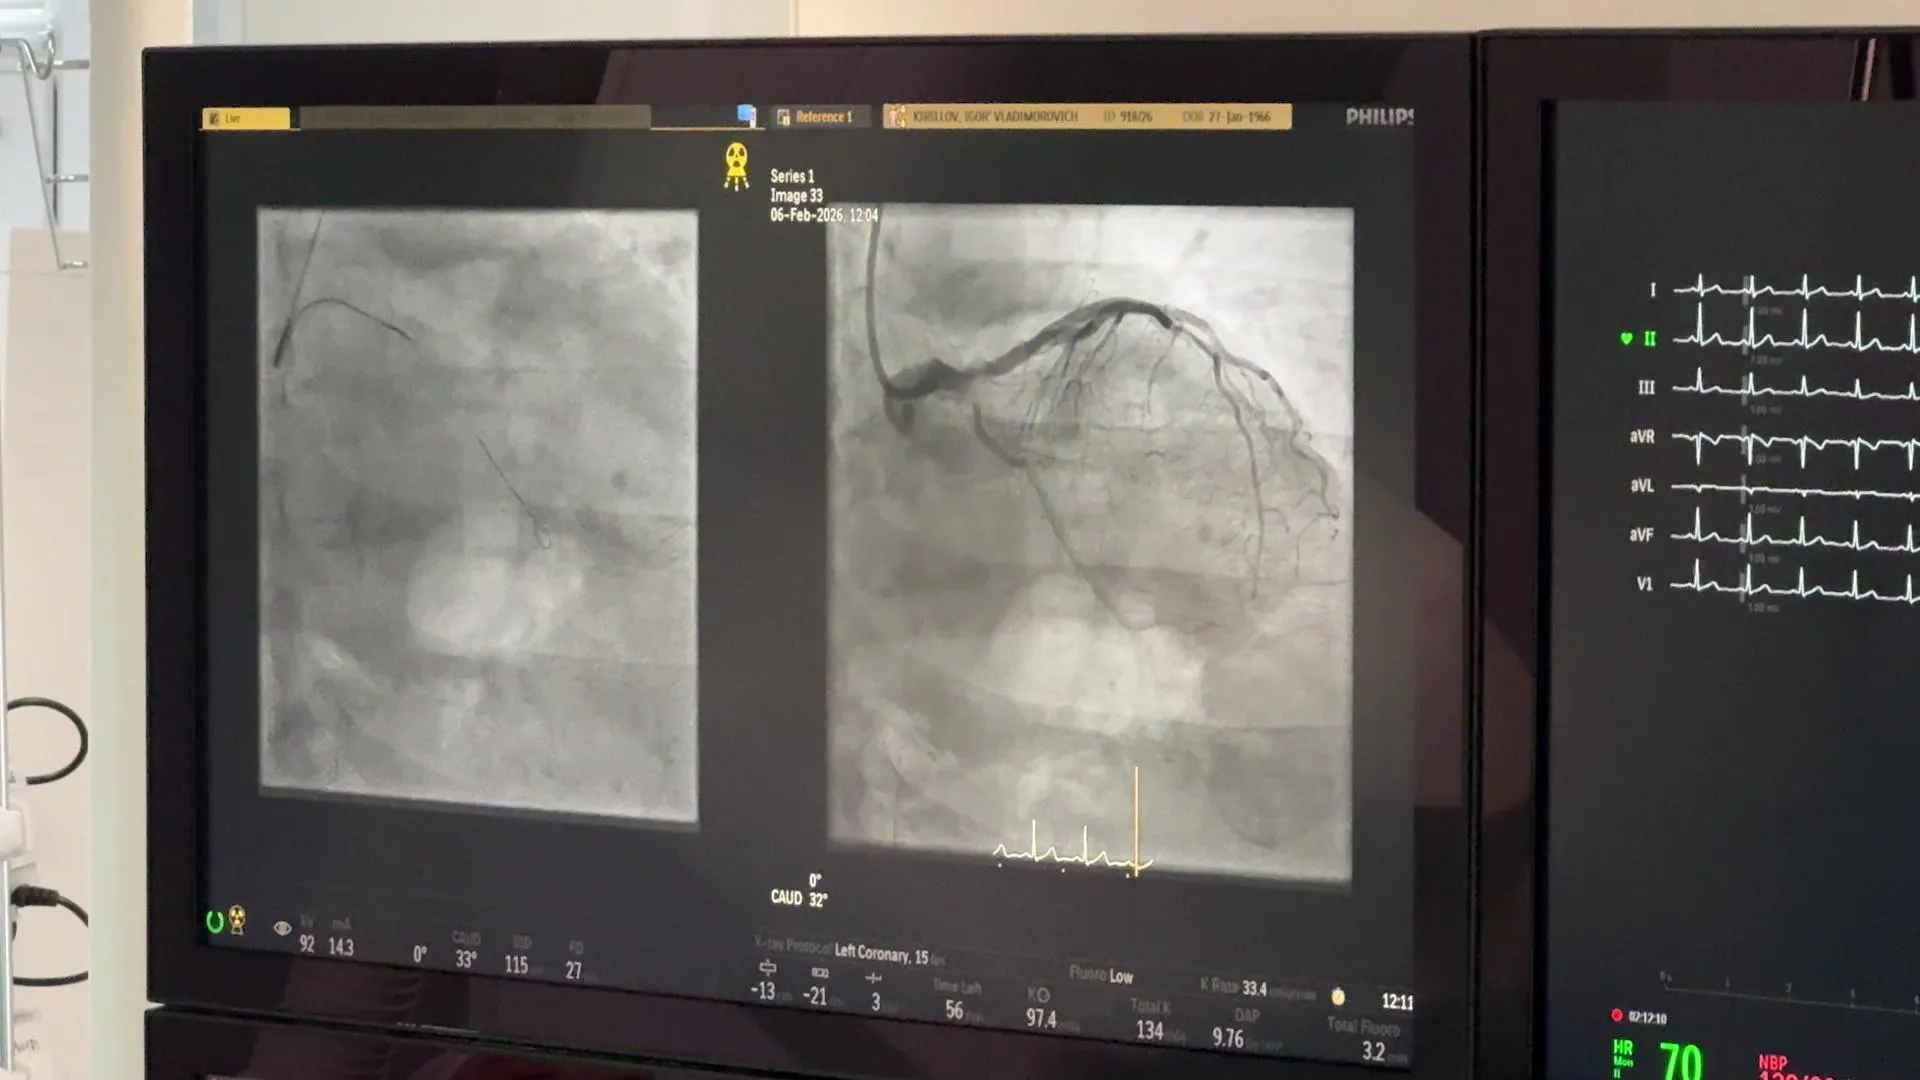

В Дубне начали проводить уникальные операции на сосудах с алмазным буромВ сосудистом центре медико-санитарной части № 9 ФМБА России в Дубне внедрили новую высокотехнологичную методику — ротационную атерэктомию для пациентов с тяжелыми формами кальциноза коронарных артерий. Первые операции проведены при участии специалиста из Федерального научно-клинического центра ФМБА России.

Процедура предполагает использование миниатюрного алмазного бура диаметром от 1,25 до 2 мм, который вращается со скоростью 130–200 тысяч оборотов в минуту. С его помощью врачи «сверлят» плотные кальцинированные бляшки, удаляя часть отложений и подготавливая сосуд к последующей баллонной ангиопластике и стентированию.

Первыми пациентами, которым понадобилась такая помощь, стали двое жителей, поступивших ранее с инфарктом миокарда. Им экстренно выполнили стентирование «виновной» артерии, а удаление кальциноза было назначено в плановом порядке. Операции прошли успешно, оба пациента уже выписаны под амбулаторное наблюдение.

Внедрению технологии способствовал Антон Стаферов, заведующий отделением рентгенхирургических методов диагностики и лечения ФНКЦ ФМБА России, чей опыт и поддержка позволили дубненскому центру освоить этот сложный метод на высоком уровне.